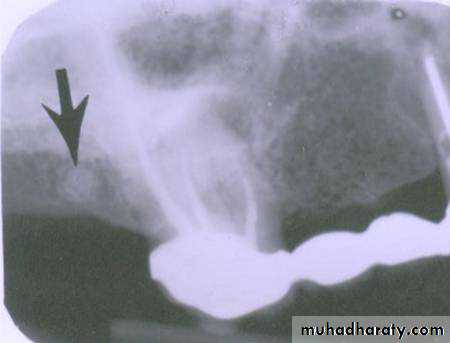

FISSURE BUR

FOREIGN BODYWATERS VIEW(Occipitomental )

LATERAL VIEWLateral oblique